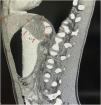

Presentamos el caso de un paciente varón de 15 años, que acude a consulta externa del Hospital Central del Estado de Chihuahua con historia de 4 meses de disfagia progresiva, síndrome anémico y pérdida de peso. Se envía a hospitalización, documentando Hb de 5.5g/dl con VCM de 74fl, HCM de 24pg y plaquetas de 500×103μl. Se transfunden 2 paquetes globulares, y se pasa a endoscopia superior, encontrando durante la retroflexión una tumoración en cardias de 6cm con mucosa de aspecto adenomatoso, friable, con sangrado durante la insuflación, se extiende hacia curvatura menor y tercio inferior de esófago, obstruyendo parcialmente la luz (fig. 1), correspondiendo a un EGJA tipo II según Siewert. La tomografía toracoabdominal mostró una tumoración gástrica de 5.7×2.6cm de aspecto infiltrativo con invasión a ganglios perigástricos, dando una clasificación cTNM de T3, N2, M0 (fig. 2). Los hallazgos de histopatología con inmunohistoquímica reportaron un adenocarcinoma moderadamente diferenciado con invasión del estroma, sin inestabilidad microsatelital, expresión integral de proteínas reparadoras del ADN y nula expresión de p53. Se administró quimioterapia preoperatoria con fluorouracilo con leucovorina, oxaliplatino y docetaxel (FLOT), hace 4 meses se realizó gastrectomía total ampliada con resección transhiatal de esófago con reconstrucción con Y de Roux retromesocólica, posterior a la cirugía se dieron 4 ciclos más de quimioterapia con esquema FLOT y actualmente en tratamiento con radioterapia con adecuada respuesta.